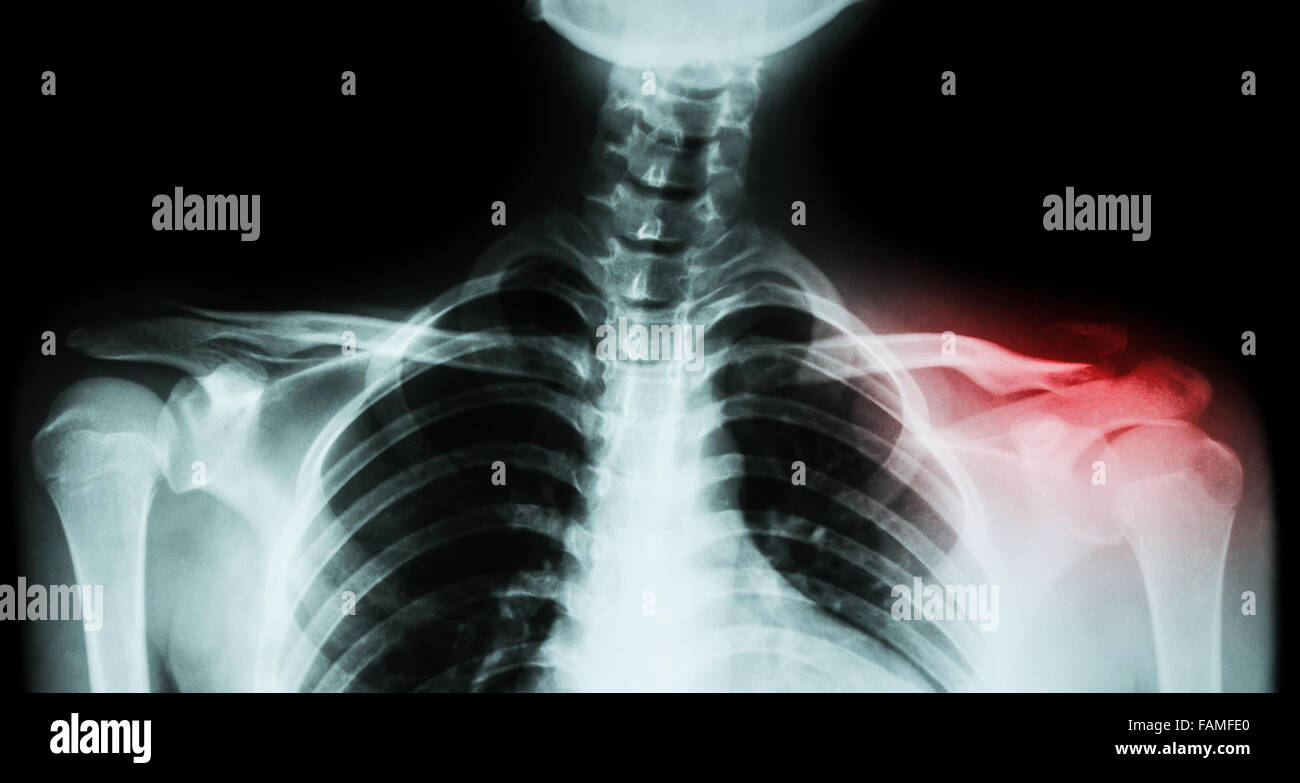

Clavicle Fracture X Ray View . The projection demonstrates the shoulder in its. The clavicle is the most proximal bone of the upper. Clavicle fractures occur commonly, often from indirect or direct trauma to the shoulder region. On the converse, radiographs are extremely difficult to interpret. The radiographic series of the clavicle is utilized in emergency departments to assess the clavicle, acromioclavicular and sternoclavicular joint. If clinical suspicion is high and if the ap view does not reveal a fracture, a 30° cephalic view can be helpful. Midshaft clavicle fractures are common traumatic injuries caused by a direct impact to the shoulder girdle and is most commonly seen in young, active adults. Clavicle fractures result in inferior displacement of the distal component. Distal clavicle fractures are traumatic injuries usually caused by direct trauma to the shoulder from a fall in adults. The clavicle ap view is a standard projection part of the clavicle series.

Midshaft clavicle fractures are common traumatic injuries caused by a direct impact to the shoulder girdle and is most commonly seen in young, active adults. The clavicle ap view is a standard projection part of the clavicle series. If clinical suspicion is high and if the ap view does not reveal a fracture, a 30° cephalic view can be helpful. Distal clavicle fractures are traumatic injuries usually caused by direct trauma to the shoulder from a fall in adults. On the converse, radiographs are extremely difficult to interpret. The projection demonstrates the shoulder in its. Clavicle fractures occur commonly, often from indirect or direct trauma to the shoulder region. The radiographic series of the clavicle is utilized in emergency departments to assess the clavicle, acromioclavicular and sternoclavicular joint. The clavicle is the most proximal bone of the upper. Clavicle fractures result in inferior displacement of the distal component.

Clavicle Fracture X Ray View The radiographic series of the clavicle is utilized in emergency departments to assess the clavicle, acromioclavicular and sternoclavicular joint. The projection demonstrates the shoulder in its. The clavicle ap view is a standard projection part of the clavicle series. Midshaft clavicle fractures are common traumatic injuries caused by a direct impact to the shoulder girdle and is most commonly seen in young, active adults. Clavicle fractures occur commonly, often from indirect or direct trauma to the shoulder region. On the converse, radiographs are extremely difficult to interpret. If clinical suspicion is high and if the ap view does not reveal a fracture, a 30° cephalic view can be helpful. The radiographic series of the clavicle is utilized in emergency departments to assess the clavicle, acromioclavicular and sternoclavicular joint. Distal clavicle fractures are traumatic injuries usually caused by direct trauma to the shoulder from a fall in adults. Clavicle fractures result in inferior displacement of the distal component. The clavicle is the most proximal bone of the upper.